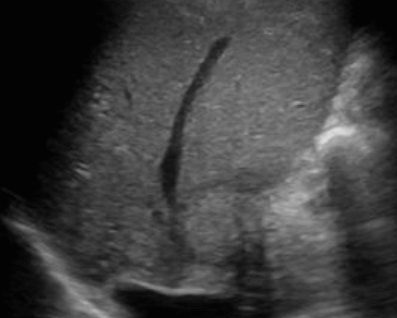

Choledocholithiasis US finding

- 총담관 내에 후방음향음영을 동반한 강한 에코가 관찰된다.

- 총담관의 확장 소견이 보인다. ( 7mm 이상)

- 담석이 관찰되지 않고 간외, 간내담관의 확장소견을 시사하는 엽총징후(shotgun sign)이나 평행관 징후(parallel channel sign)가 관찰되기도 한다.

- 엽총징후(shotgun sign): 간외 담관이 확장되어 간외 담관과 문맥이 이웃해 관찰된다.

- 평행관 징후(parallel channel sign): 간내 담관이 확장되어 인접하고 있는 문맥과 나란히 2개의 관상구조로 나타난다.